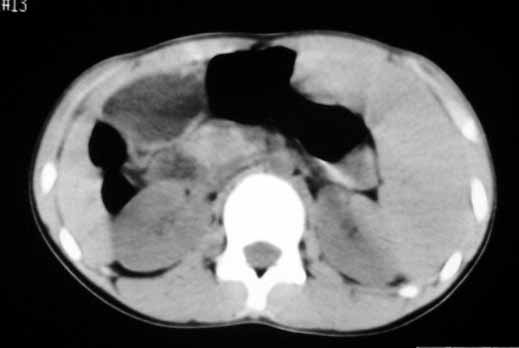

以下是引用zhangzhongshou在2007-5-22 21:04:00的发言:[br]1、脾肿大[br]2、脾脏低密度影,血管瘤?脾梗塞不能除外,建议增强扫描。

以下是引用dyqct在2007-5-22 20:45:00的发言:[br]巨脾,可疑梗塞,建议增强、查血象进一步检查

以下是引用liuyue在2007-5-23 7:57:00的发言:[br]腹主动脉周多个肿大淋巴结,脾大伴三角形低密度影,肠腔积气,考虑:1淋巴瘤2脾大伴梗塞3肠腔积气(肿大淋巴结压迫所致)